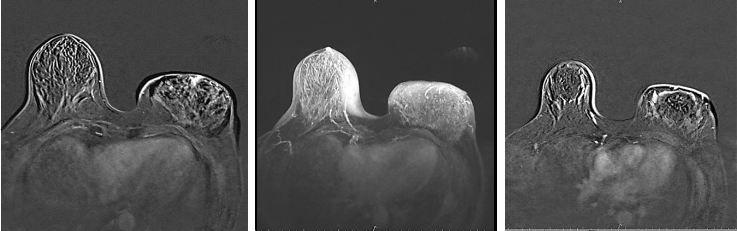

乳腺增强MRI提示左乳皮肤及乳晕增厚,乳头略凹陷,皮下腺体结构紊乱。左乳较右侧明显增大。左乳可见巨大肿块影,大小约12.3cm×6.7cm,T1WI呈等信号,T2WI呈稍高信号,局部DWI呈高信号,ADC减低,增强后明显不均匀强化,时间信号曲线呈平台型。左腋下可见多枚淋巴结影,最大者约2.1cm×1.4cm,BI-RADS 5(图4)。

图4.乳腺增强MRI

图7.新辅助治疗2周期后的乳腺增强MRI评估

图8.新辅助治疗6周期后的乳腺增强MRI评估